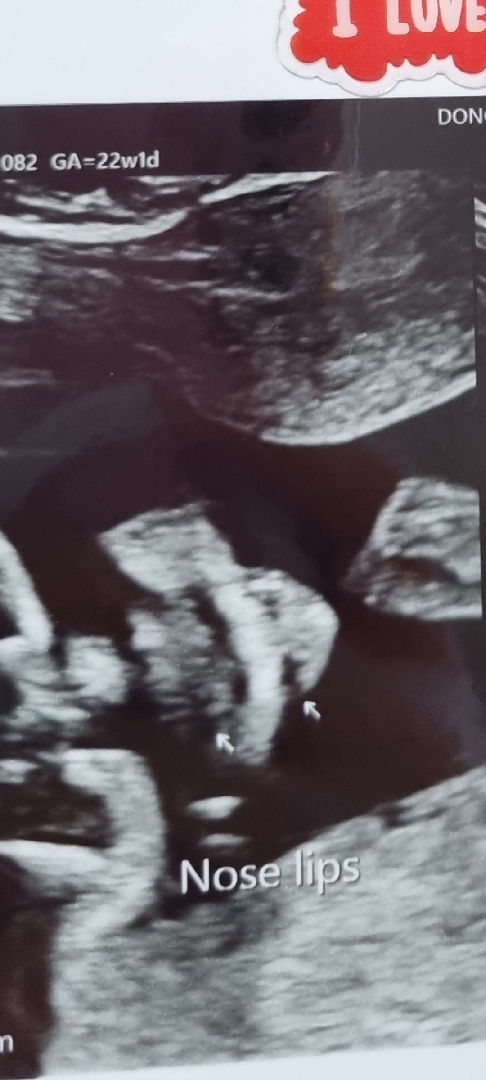

오늘 정밀초음파 보고왔는데, 집에 와서 생각해보니 언청이인지 입술이 괜찮은지는 말씀을 안해주셨어요ㅠㅠ 이 입술모양이면 정상인걸까요? 입술이랑 콧구멍입니다~

코구멍 밑에 하얀 부위가 인중(위턱뼈)위치 하얗게 잘보이면 건강한 아가예요~

콧구멍 밑에 입술라인이 확실하게 보이면 정상이라구 그러셨어요! 구순열까지는 정밀촘파로 확인하고 24주 입초때 구개열까지 있는지 확인할 스 있다던데 보통 구순열에 문제 없으면 무난히 통과래요!

언청이는 아닌거같아용 ㅎㅎㅎ 말씀 안해주신거면 괜찮은거아닐까용?? 글구 언청이였으면 갈라진게 확 보였을거에용 ㅎㅎㅎ